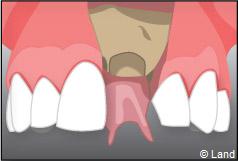

Exemple d’un implant unitaire pour remplacer une dent antérieure manquante.